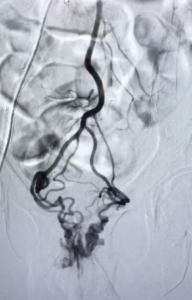

Contrôle artères rectales supérieures après embolisation